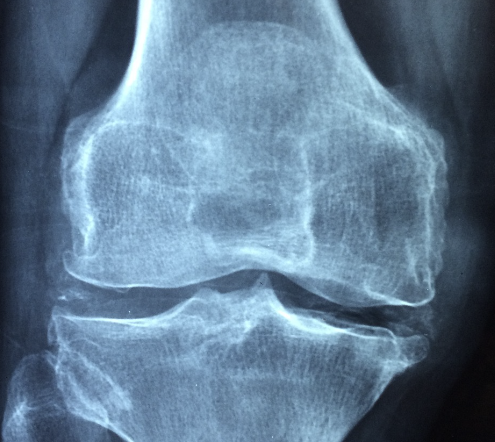

프롤리아는 골다공증 치료제로 6개월에 한 번 피하주사로 투여하는 약물입니다. 프롤리아의 성분은 데노수맙이라는 인간 단일클론항체로, 골을 파괴하는 세포의 활성을 억제하여 골흡수를 줄이고 골밀도를 증가시킵니다. 프롤리아는 2019년 4월부터 골다공증 치료제 1차 약제로 보험 인정이 되었으며, 폐경 후 여성과 남성 골다공증 환자에게 사용할 수 있습니다.

- 척추, 고관절, 비척추 골절의 위험을 각각 68%, 40%, 20% 감소시킵니다12.

- 요추와 고관절의 골밀도를 10년 간 치료적 정체 없이 각각 21.7%, 9.2%로 유의하게 증가시킵니다3.